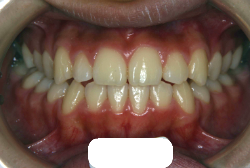

「歯並びの凸凹を直したい」という主訴で来院したケースです。診断の結果、たしかに「叢生」という隙間が足りないと言うことが原因の凸凹症例でした。

しかし、それ以上に問題なのは「前歯の噛み合い方が深すぎる」という症状で、初診の歯の正面写真を見ると下の前歯が全く見えません。こういう症状を矯正学では「過蓋咬合(かがいこうごう)」と言います。過蓋咬合を放置すると、将来的に顎関節に悪影響を与えるとされており、顎関節症の原因因子の一つです。また下の前歯の先端が、上の前歯の裏側の歯茎と強く接触するため、歯周病の原因にもなります。

検査の結果、凸凹が軽症なため非抜歯で矯正すること可能と判断、マルチブラケット装置にて治療しました。治療後は歯並びが綺麗になっただけでなく、噛み合わせ的にも正しい状態が確立しています。